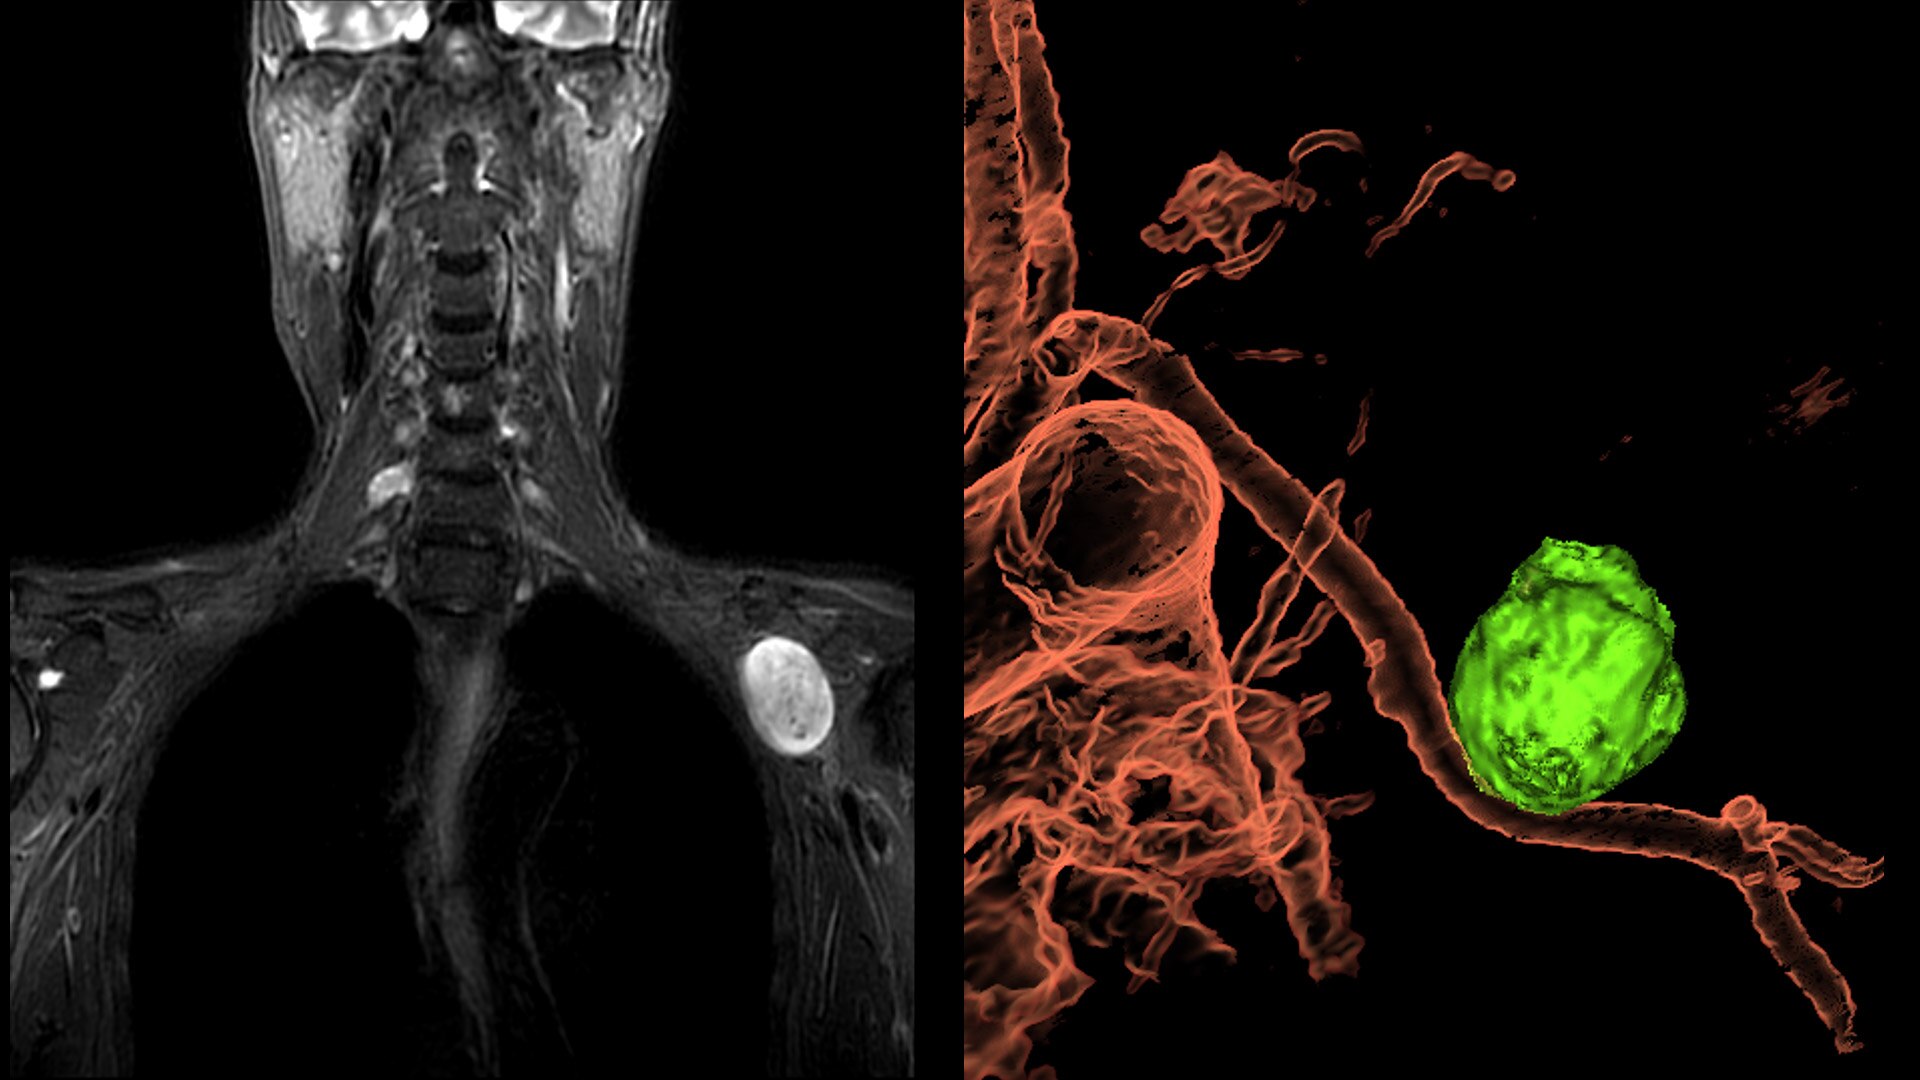

An award-winning industry first in MRI coils. With overlapping, ultra-light, flexible coil elements at their heart, AIR™ Coils deliver an MRI experience that gets closer to your patient, so you get closer to the truth. Representing a new standard in MRI coil technology, AIR™ Coils enable a simplified, faster workflow while maintaining excellent image quality. Scan complex anatomies and complicated conditions in a variety of patient sizes with exceptional results.

Every time we found ourselves starting to compromise, we started over

• Positioning freedom with previously hard-to-scan anatomies

With AIR™ Recon DL and AIR™ Multi-Purpose Coils, Maçka EMAR Diagnostic Center observed a reduction of 40-50% less scan time on average for all anatomies.